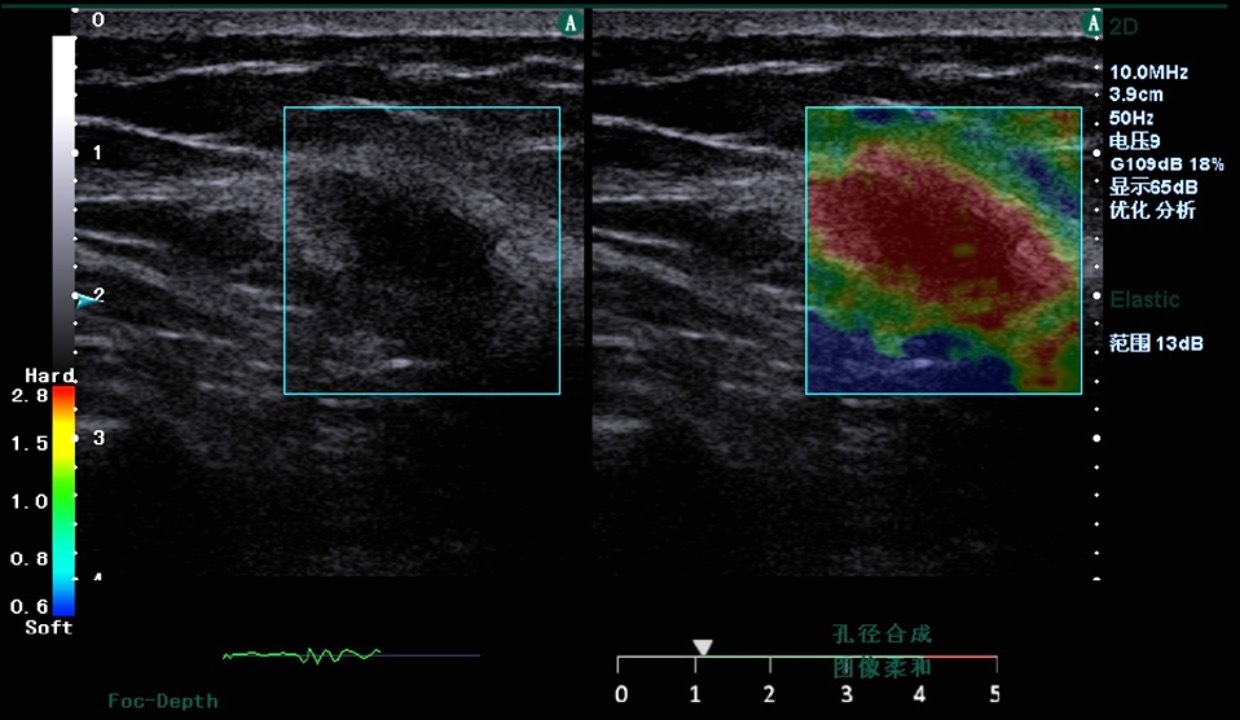

实时弹性成像

基于声能实时弹性成像技术,可以提供快速精准的实时定量弹性图像,为临床提供组织软、硬病变的定量评价,实现临床快速精准诊疗